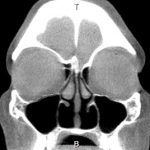

A imagem do paciente mostrado abaixo foi submetida a septoplastia com ressecção agressiva de concha na década de 1980. Esse era um procedimento popular na época, mas foi abandonado na década de 1990 devido à alta incidência da síndrome do nariz vazio. Os cornetos inferiores estão ausentes e os médios estão inchados, contribuindo para um nariz bem aberto e seco, que se sente entupido e goteja constantemente.